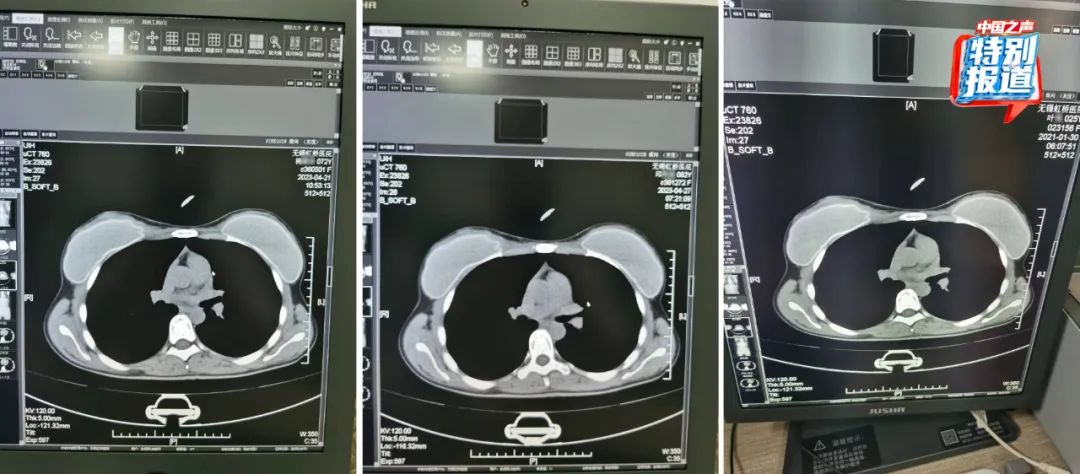

在被举报的病历中,杨某某(72岁)和邱某某(62岁)的病历里,有根据所拍片子的情况做出的诊断,却找不到对应的影像。6月份又查到了她们的CT影像,按照系统记录,这两人都是2023年4月做的胸部CT,片子上能清晰看出,两位患者的吊坠形状、大小和位置都基本一致。

不仅这两位上了年纪的患者CT影像类似,朱成刚比对发现,2021年在他们科做过CT的25岁女性叶某的片子上,也有看起来极为相似的吊坠,肉眼看,三人的片子几乎一模一样。

患者李某某在2023年4月28日拍摄了胸部CT,她的影像与实际患者刘某在2024年2月的检查影像看起来高度相似。

74岁的患者莫某在2023年4月27日拍摄了胸部和颈椎的CT,她的片子看起来和实际患者37岁的马某某在2023年11月拍的片子高度相似,片子里能直观看到项链都一模一样。